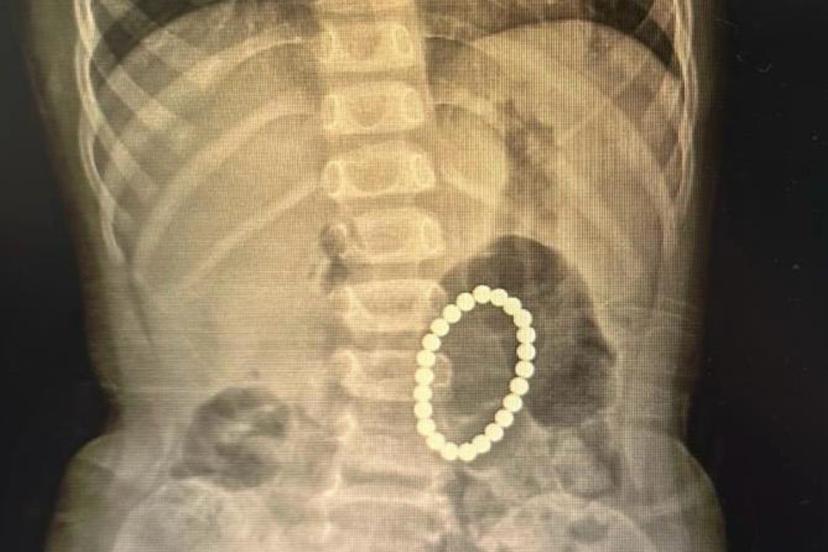

Çocuklarda sık karşılaşılan risklere değinen Özkaya "Günlük hayatta çocuklarda sık karşılaşılan yabancı cisim yutulması, kimyasal madde içilmesi ve solunum yollarına yabancı cisim kaçması önemli sağlık sorunları arasında yer almaktadır. Özellikle ilk üç yaşındaki çocuklar, yerde buldukları nesneleri ağızlarına götürme eğilimindedir. Madeni paralar, disk piller, iğneler ve küçük oyuncak parçaları çocuklar tarafından yutulabilmekte; bu maddeler yemek borusuna ya da solunum yollarına kaçabilmektedir. Bu tür durumlarda ailelerin olaya şahit olmaları hâlinde çocuğun ağzını kontrol etmeleri, yutma şüphesi varsa vakit kaybetmeden en yakın sağlık kuruluşuna başvurmaları gerekmektedir." dedi.